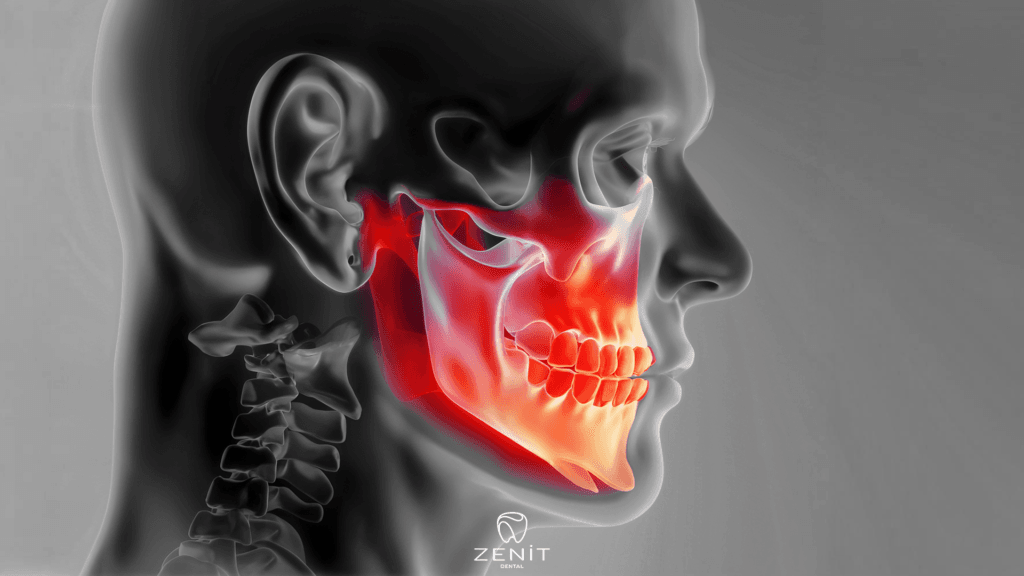

İltihaplı Diş Ağrısı

İltihaplı diş ağrısı, genellikle diş eti enfeksiyonlarından kaynaklanan ciddi bir rahatsızlıktır. Bu tür ağrılar, günlük yaşamı olumsuz etkileyebilir ve tedavi edilmediğinde daha ciddi sorunlara yol açabilir. Ancak, doğal yöntemlerle iltihaplı diş ağrısını hafifletebilir ve rahatlama sağlayabilirsiniz.